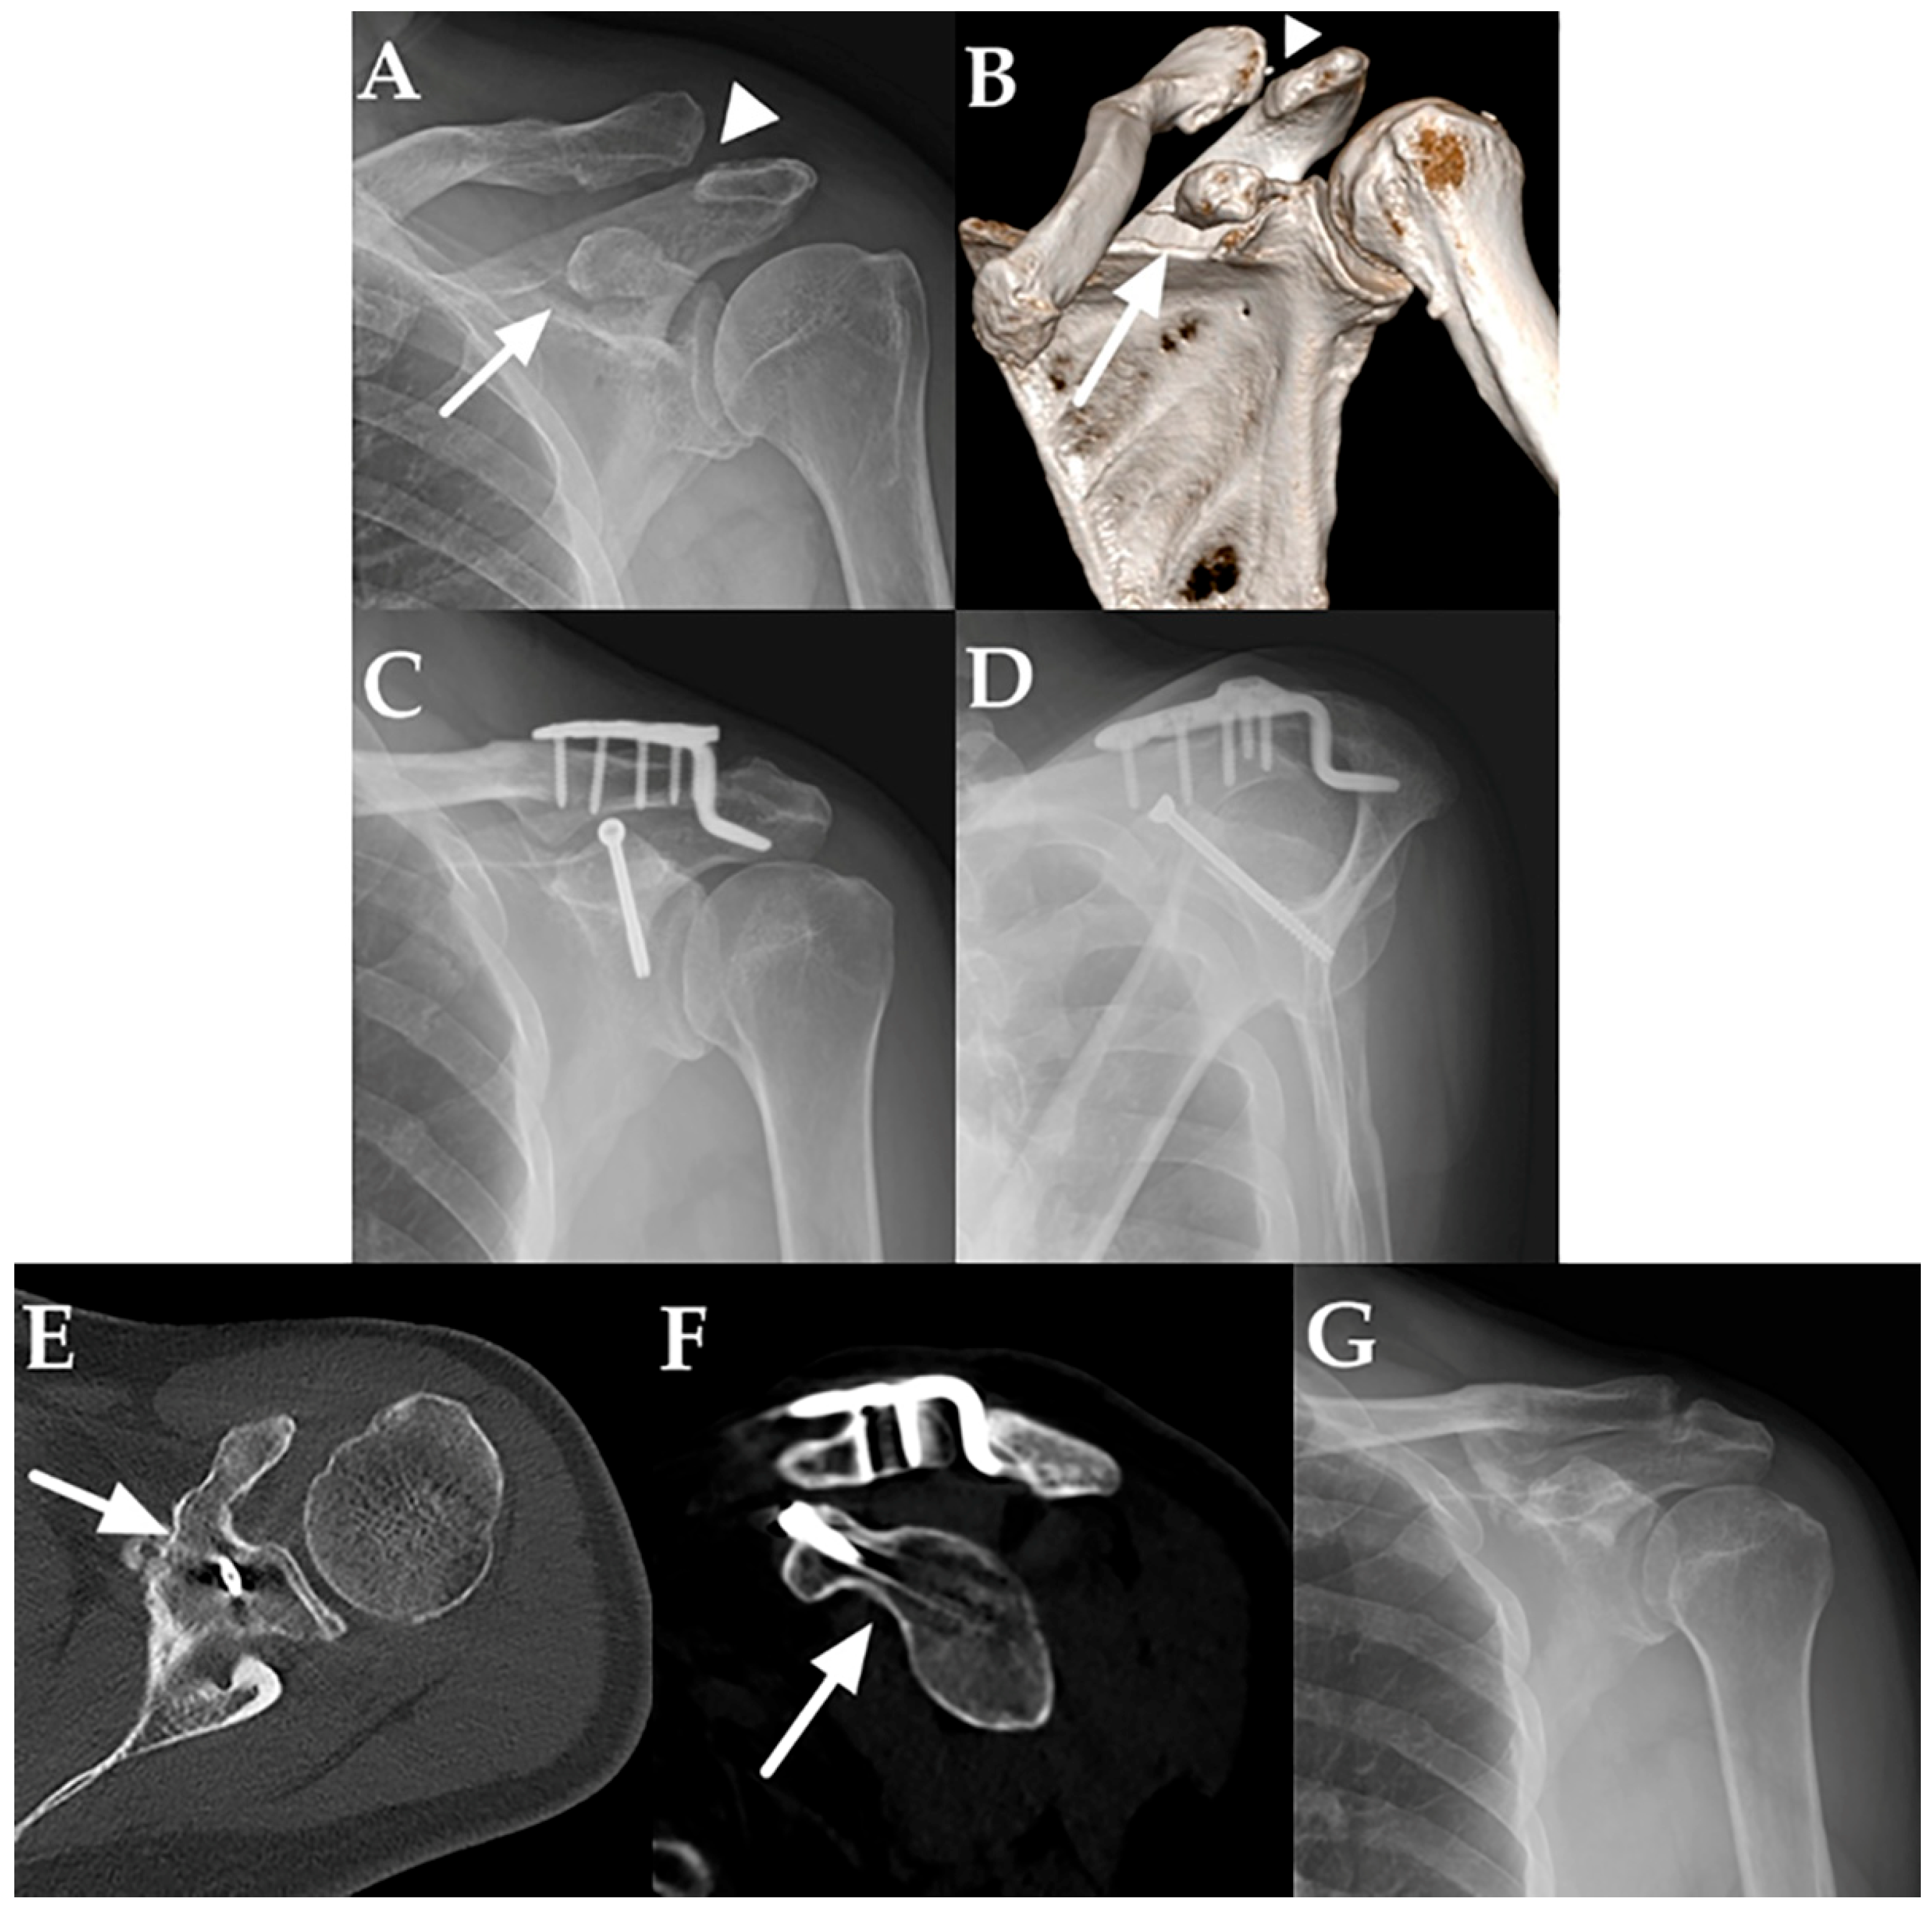

2.2. Surgical Technique and Rehabilitation

3.3. Radiologic Outcomes